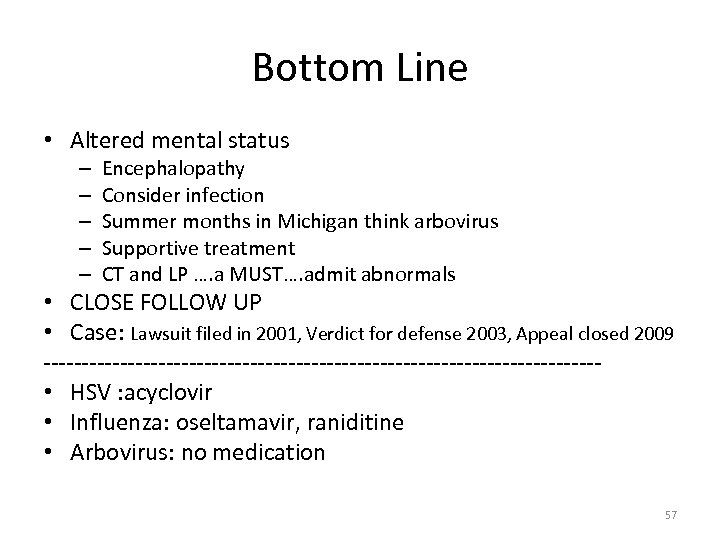

Bottom Line • Altered mental status – – – Encephalopathy Consider infection Summer months in Michigan think arbovirus Supportive treatment CT and LP …. a MUST…. admit abnormals • CLOSE FOLLOW UP • Case: Lawsuit filed in 2001, Verdict for defense 2003, Appeal closed 2009 ------------------------------------ • HSV : acyclovir • Influenza: oseltamavir, raniditine • Arbovirus: no medication 57